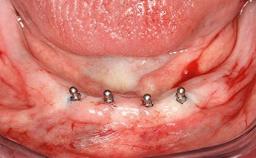

In 2007, a 97-year-old patient presented for treatment at the Geneva Dental School. His dentist had retired. Like many elderly patients, he was left without regular dental care. He lived on a geriatric ward, as he was partly dependent on help with most of the activities of daily living (ADL), such as getting dressed, washing, taking a shower, or climbing stairs. However, he was able to go to the bathroom and get up from bed on his own (ADL score 80, min. 18, max. 126; a low score signifies a high degree of dependency) (Lawton and Brody 1969). He was not bound to a wheelchair, but used a walker. Moreover, he was socially highly active—his family visited on a regular basis and he often went to the restaurant with his friend, who was some 20 years younger. His cognitive function did not seem to be impaired in a normal conversation, although his MMSE score was only 21/30 at that time (Folstein and coworkers 1975). The patient was a retired pharmacist, and his latest passion was astronomy.

Case Type Edentulous Mandible

Jaw Mandible

Area Full-Arch

# of Teeth All

# of Implants 2

Type of Implants One-Piece

Defining Characteristics Fully edentulous lower jaw to be rehabilitated with two or more implants

Modality 2 interforaminal implants